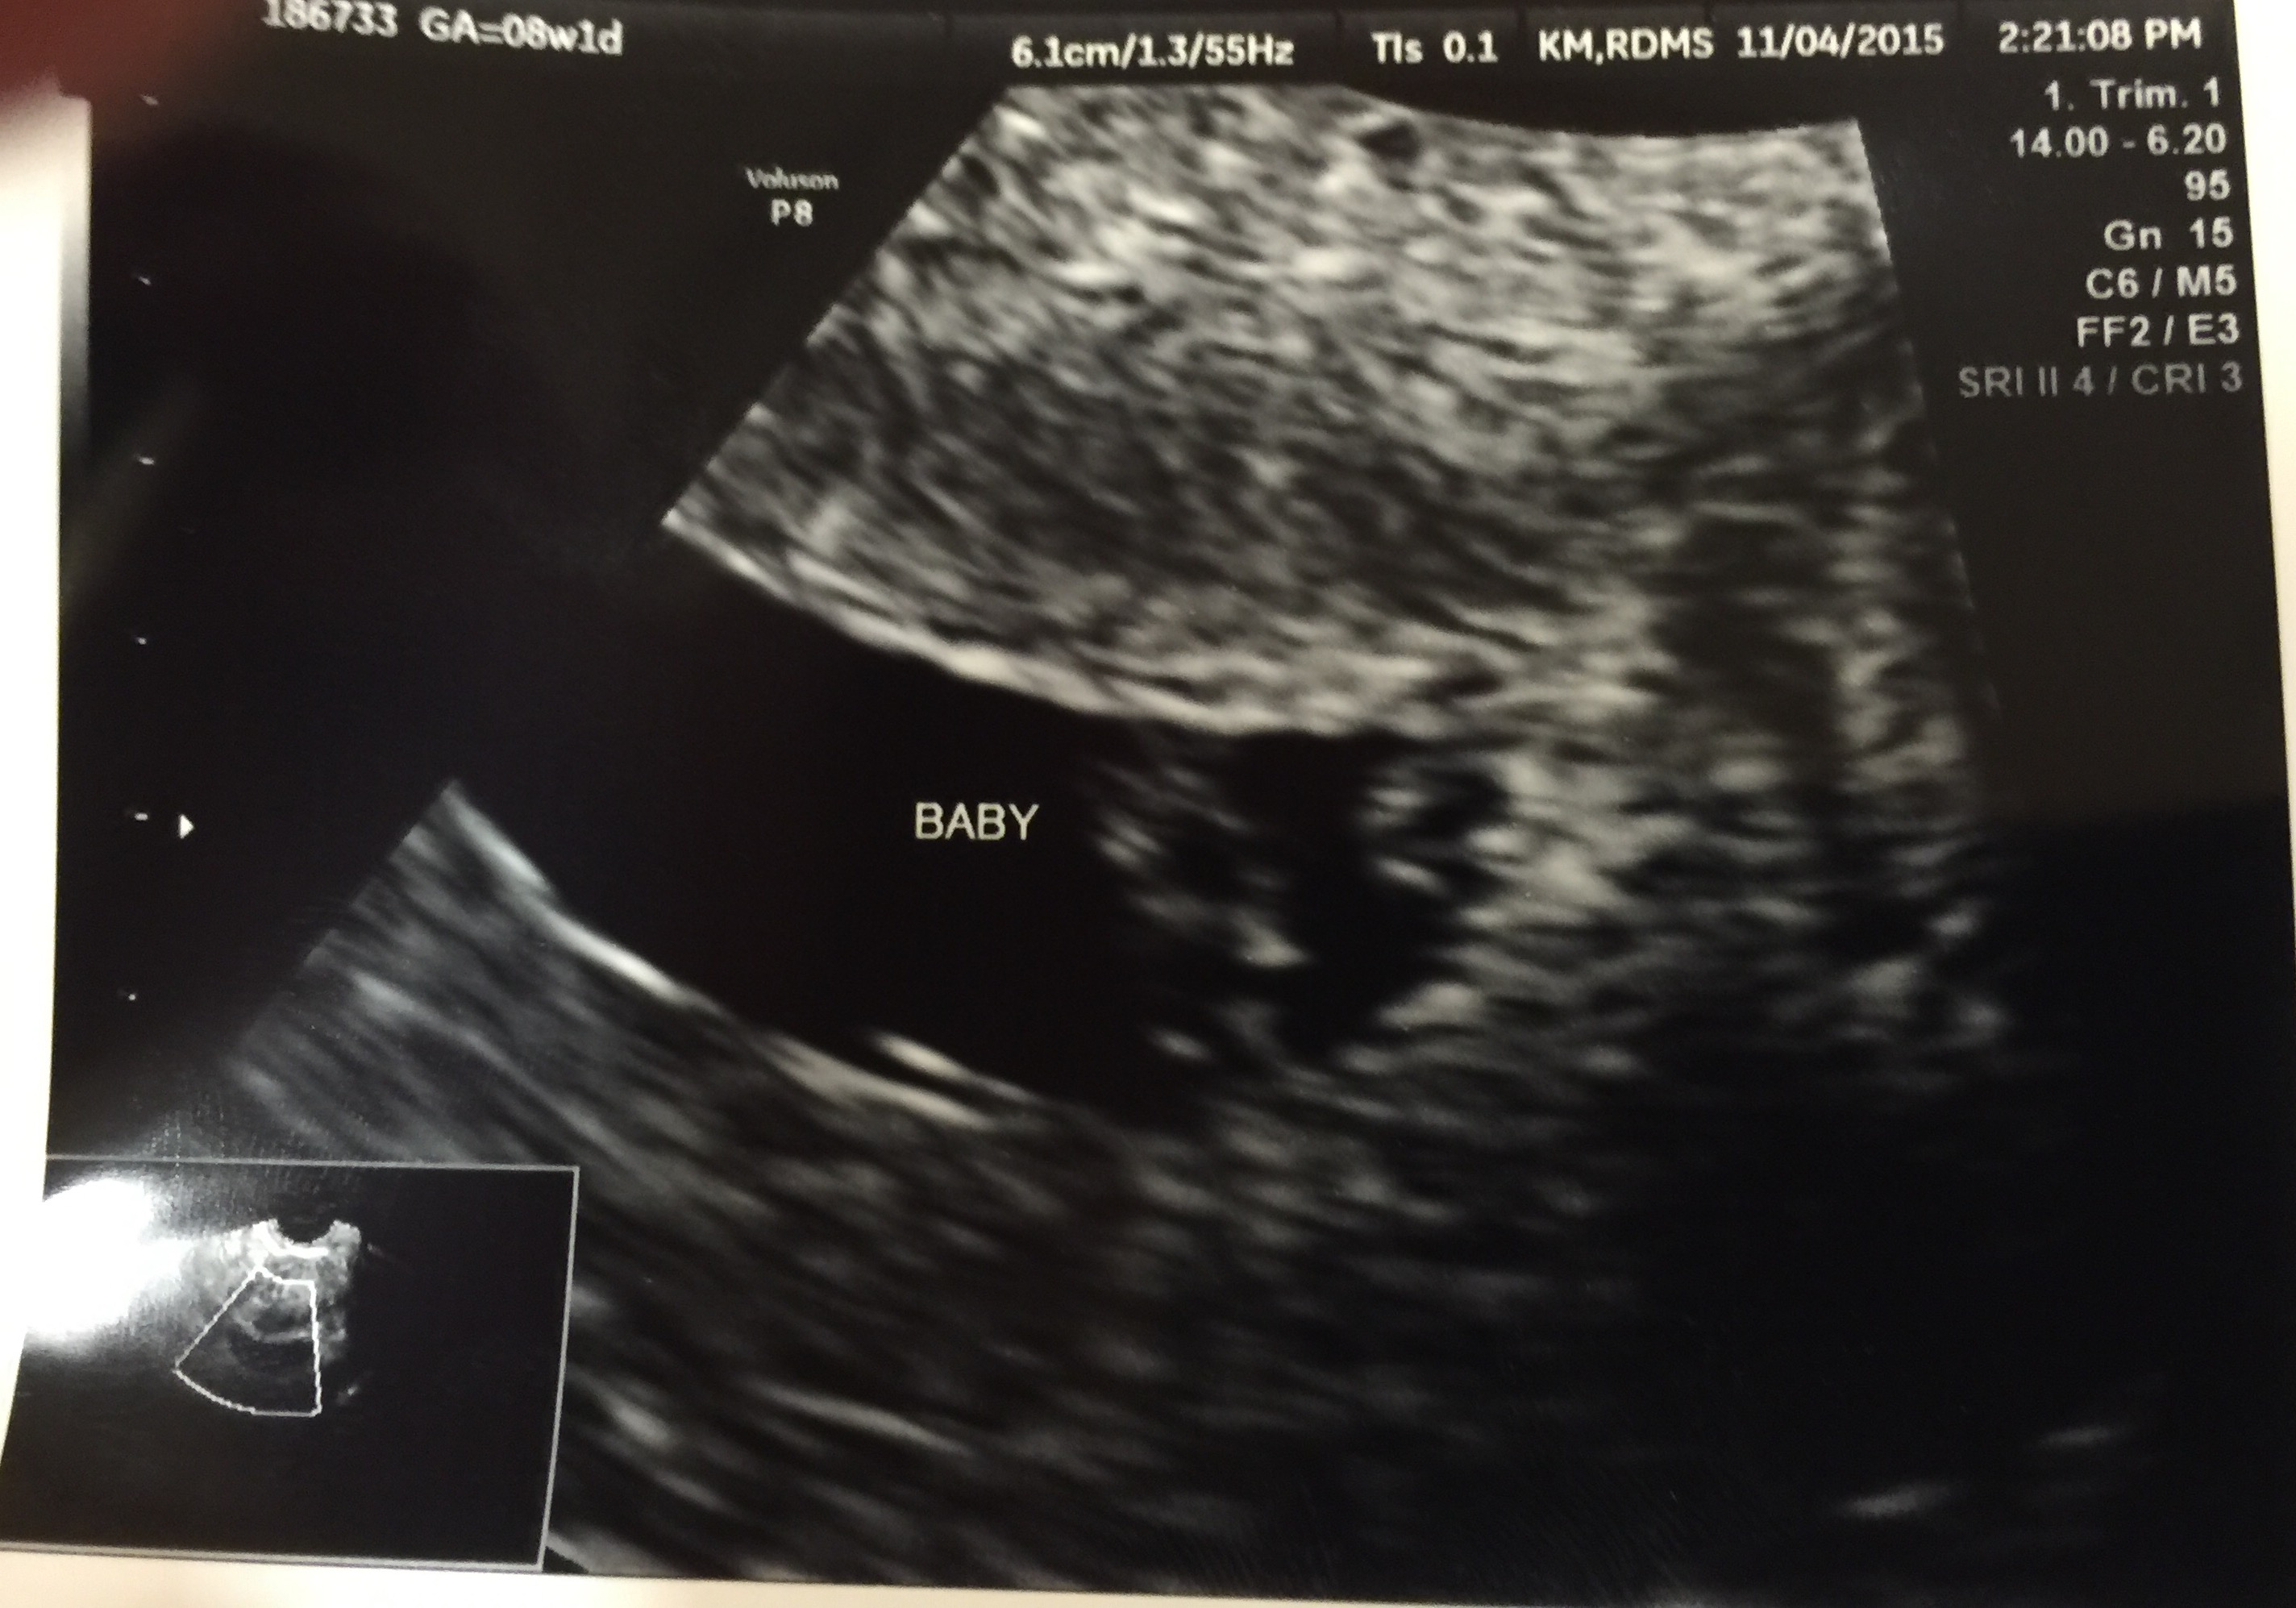

FTM! So excited to see how much my little gummy bear has grown in two weeks! 1st pic is at 6w5d, HR 147, and just a little blob with a flickering heart. 2nd & 3rd pics are at 8w5d, HR 176, and looked so much like a tiny baby with bitty arms and legs. Doc says baby is healthy and quite a dancer, it was moving and waiving all over the place. What a blessed moment to see!